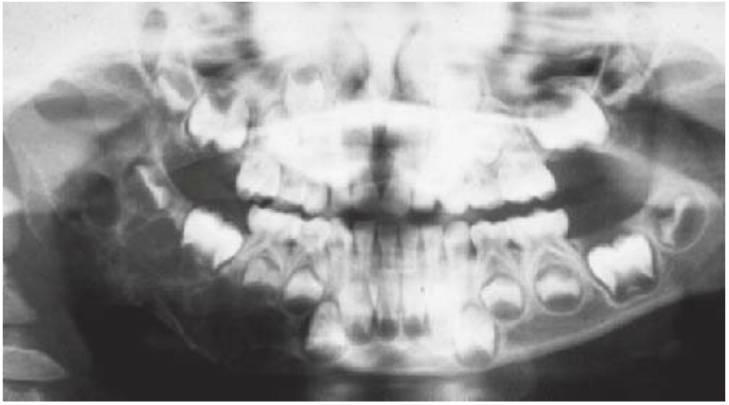

La asistencia clínica global de un niño con problemas médicos requiere la consideración de la afección sistémica subyacente y la coordinación de su tratamiento dental con su médico. Aunque las alteraciones dentales son frecuentes en este grupo de pacientes, su salud es pasada por alto con frecuencia por los profesionales clínicos. El término que se solía emplear para identificar a este conjunto, «niños con problemas médicos», ha sido recientemente sustituido por el de «niños con necesidades especiales». Sin embargo, el primero de estos términos aún mantiene su vigencia, ya que recuerda al dentista que estos niños con frecuencia padecen alteraciones médicas que pueden afectar a su tratamiento dental o que pueden presentarse con manifestaciones orales específicas de una enfermedad sistémica. El presente capítulo analiza las enfermedades pediátricas habituales que han de tenerse en cuenta en el marco de un tratamiento dental óptimo. La prevención de las enfermedades de la boca es importante en niños con problemas médicos crónicos (fig. 10.1), ya que las complicaciones orales pueden comprometer gravemente el abordaje terapéutico médico y el pronóstico general de un niño.